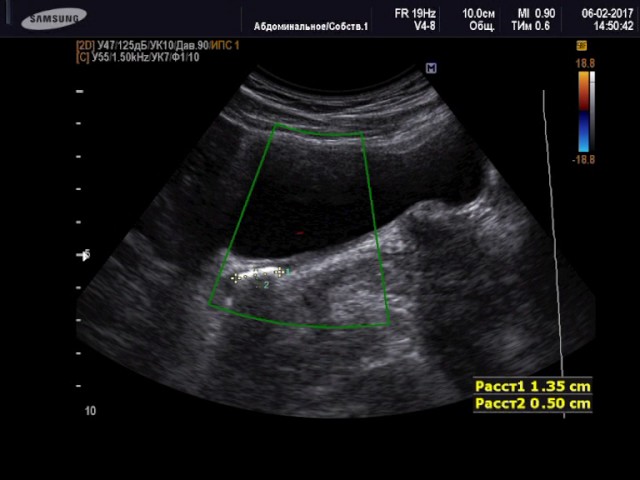

С помощью УЗИ можно определить, в каком месте мочеточников локализуются конкременты и какого они размера. Эхогенная плотность мочеточников в норме отличается от состояния, когда в них находятся камни или песок. Если же в них образовалась опухоль, то на УЗИ можно зафиксировать изменение контура мочевыводящей трубки.

На УЗИ мочеточники видны как эхогенное образование темного цвета с гиперэхогенными стенками, визуализирующиеся светлым оттенком. Распространенной патологией мочеточников, выявляемой посредством УЗИ, является их непроходимость. Такое нарушение является симптомом следующих заболеваний мочеточников: